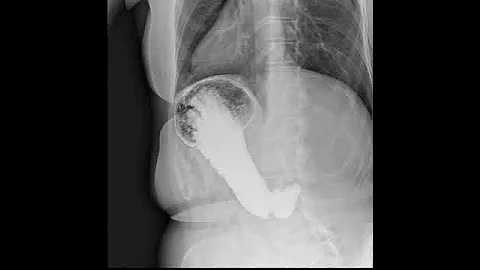

Dynamic X-ray Retrospective View Of The Esophagus In Motion | Konica Minolta Healthcare

Experience the incredible detail of Dynamic Digital Radiography (DDR) technology as we take a Retrospective look at the ...